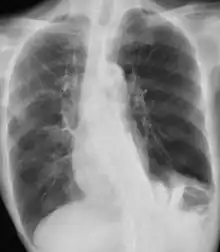

Chest X-ray in a case of COPD exacerbation where a nasopharyngeal swab detected Haemophilus influenzae, with right-sided opacities

A chest X-ray is usually performed on people with fever and, especially, hemoptysis (blood in the sputum), to rule out pneumonia and get information on the severity of the exacerbation. Hemoptysis may also indicate other, potentially fatal, medical conditions.[6]